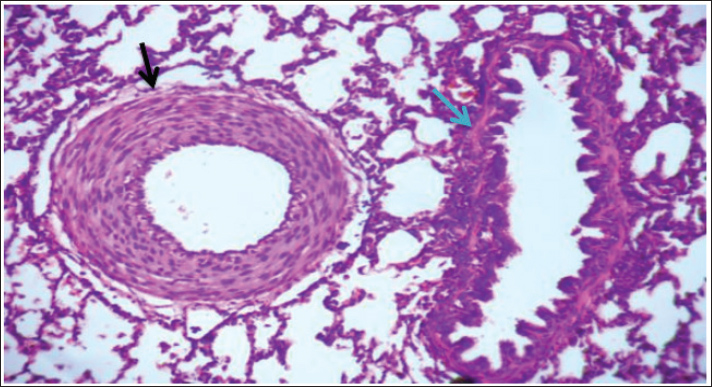

The Vitek2 system provided reliable identification (93% probability), supporting the accuracy of the isolates used in this study. The antimicrobial susceptibility profile revealed varying resistance patterns, which may have clinical implications for treatment strategies. Further studies are needed to explore the virulence mechanisms and potential zoonotic risks associated with Raoultella planticola. Histopathological resultsHistological examination of lung tissue revealed emphysema and atelectasis (Fig. 6A and B). Emphysema was characterized by permanent enlargement of air spaces distal to the terminal bronchioles, accompanied by destruction of alveolar walls without significant fibrosis.

Fig. 6. Group of infected rabbits lung (A) Bronchiols show emphysema aggregation of lymphocytic cell (black arrow)( B) show emphysema structure atelectasis (black arrow) H&E stain 400X and lung H&E stain 200X. Gross examination of sacrificed animals (group of infected rabbits) showed hemorrhage in the upper respiratory tract (Fig. 3). The trachea exhibited a semi-circular hyaline cartilage structure (Fig. 4), and the bronchi branched into left and right bronchioles, consistent with typical mammalian respiratory anatomy. Normal histological details of trachea of control group• Tunica mucosa • Tunica submucosa • Tunica adventitia • C-shaped hyaline cartilage (Fig. 5A) • score lesion of Pathological Changes • Emphysema was observed in 3 out of 5 cases (60%) (Fig. 4). • No pathological changes were seen in 2 cases (40%). • Vascular changes, including congestion, thrombosis, and alveolar hemorrhage, were noted in 10% of affected cases. Comparative morphologyLight microscopy analysis confirmed Gram-negative rods for Raoultella planticola. However, differentiation from Klebsiella spp. was challenging due to morphological similarities (Fig. 2A and B). The histological findings of emphysema and atelectasis align with Blagojević et al. (2018), who described similar structural changes in respiratory infections. The observed hemorrhage and vascular congestion support Castro et al. (2001), who linked these changes to bacterial-induced trauma. The 60% incidence of emphysema suggests that Raoultella planticola primarily induces chronic obstructive pulmonary disease (COPD)-like lesions, differing from Sarhad (2011), who reported fibrinous pleuropneumonia as the dominant pathology. This discrepancy may stem from differences in infection routes or host susceptibility. The short respiratory passage and direct bronchial branching in rabbits (Abdelsalam and Al Sadrani, 2015) likely contribute to higher lung infection rates. Additionally, the similarity between Raoultella and Klebsiella (Alampoondi Venkataramanan et al., 2021) complicates microscopic differentiation, necessitating advanced diagnostic methods like Vitek2.Contrary to Vinshia, J. J., (2024), this study found no fibrinous bronchopneumonia, instead emphasizing edema and congestion (Das and Bhagman, 1997). The reclassification of Raoultella from Klebsiella prior to 2001 further underscores the need for precise microbiological identification (Fig. 8). This study highlights Raoultella planticola's potential to cause respiratory pathology, warranting further investigation into its zoonotic risks.

Fig. 7. The lung is show emphysema group of infected rabbits show moderate fibroplasia of arterioles. (black arrow) and tertiary bronchioles (blue arrow). H&E stain 400X (Castro et al., 2001).